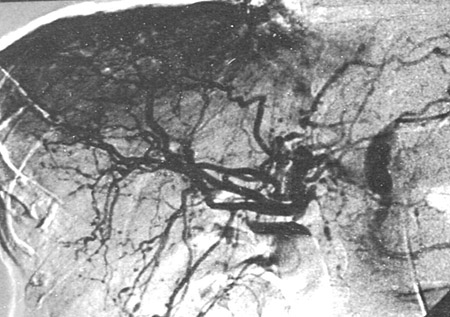

Angiografia mesentérica mostrando pequenos aneurismas e microaneurismas

Do acervo do Dr Loic Guillevin